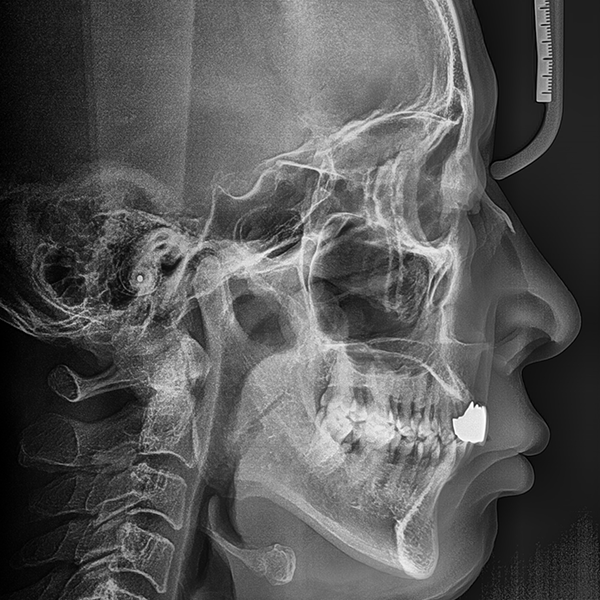

上顎/前牙部位 / 3顆以下 / 補骨|高血壓

案例.110 60多歲 李*桂 2020-01-20 / 2020-3-21